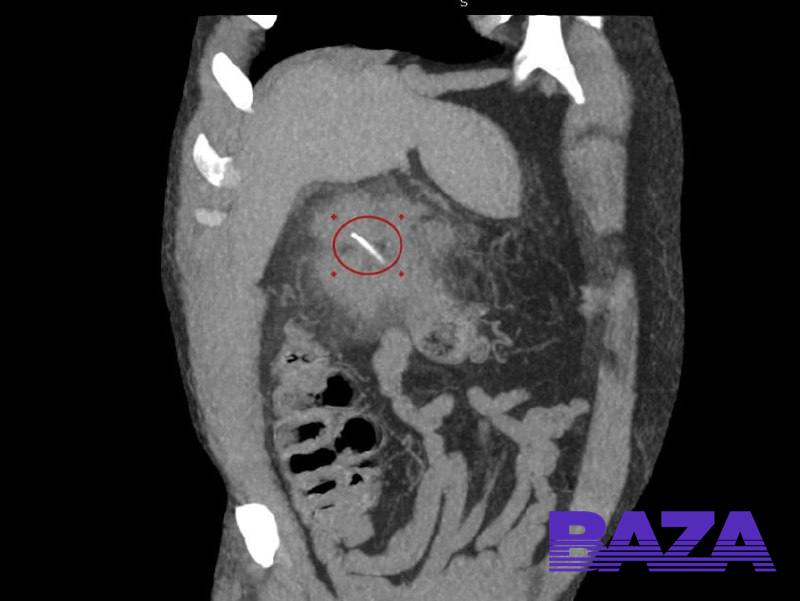

Ռուսաստանում ձկնորսը ընթրիքին տապակած ձուկ ուտելուց պատահաբար ոսկոր է կուլ տվել, և այն ծակել է նրա աղիքները (Լուսանկար)

Մոտ մեկ ամիս առաջ 64-ամյա տղամարդը հաջող ձկնորսություն է անցկացրել և ընթրել թարմ ձուկով։ Մի քանի շաբաթ ամեն ինչ կարգին էր, բայց հետո ձկնորսը սկսեց իր հիպոքոնդրիումում քորոց զգալ։ BAZA տելեգրամ ալիքի տեղեկություններով՝ սկզբում տղամարդը համբերել է, բայց երբ ցավն անտանելի է դարձել, նա դիմել է հիվանդանոց։

Բժիշկները զննել են հիվանդին և հայտնաբերել ցավի պատճառը՝ պարզվել է, որ դա ձկան ոսկոր է։ Նա ծակեց աղիքները և մոտեցավ լյարդին։ Լուխովիցկիի հիվանդանոցի բժիշկները ողնաշարի անզգայացման տակ բացել են թարախակույտը և հեռացրել ոսկորը։ Ձկնորսն արդեն ապաքինվում է։ Թվում է, թե վիրահատությունից հետո առաջին անգամ նա կընտրի միայն ֆիլե։